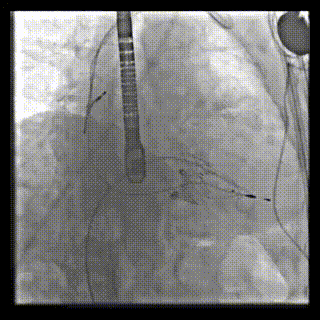

本周三例接受LuX-Valve Plus經(jīng)血管三尖瓣置換術(shù)的患者中,第一例患者為冠狀動(dòng)脈旁路移植術(shù)+Bentall+二尖瓣成形術(shù)后;第二例患者為永久起搏器植入術(shù)后,存在跨三尖瓣導(dǎo)線;第三例患者合并房顫、房缺及左心耳封堵術(shù)后。

三例患者入院后,葛均波院士團(tuán)隊(duì)周達(dá)新教授、潘文志教授、張?jiān)床┦?、陳莎莎博士及心超室的潘翠珍教授、李偉教?/strong>對(duì)患者的情況進(jìn)行詳細(xì)評(píng)估和討論,最終決定為三例患者選擇LuX-Valve Plus40mm、50mm和50mm型號(hào)的瓣膜進(jìn)行手術(shù)治療。手術(shù)后即刻拔除氣管插管,術(shù)后患者三尖瓣反流癥狀得到顯著改善,復(fù)查心超結(jié)果顯示人工三尖瓣瓣膜支架固定穩(wěn)定,瓣葉關(guān)閉形態(tài)未見(jiàn)異常,未見(jiàn)明顯反流。